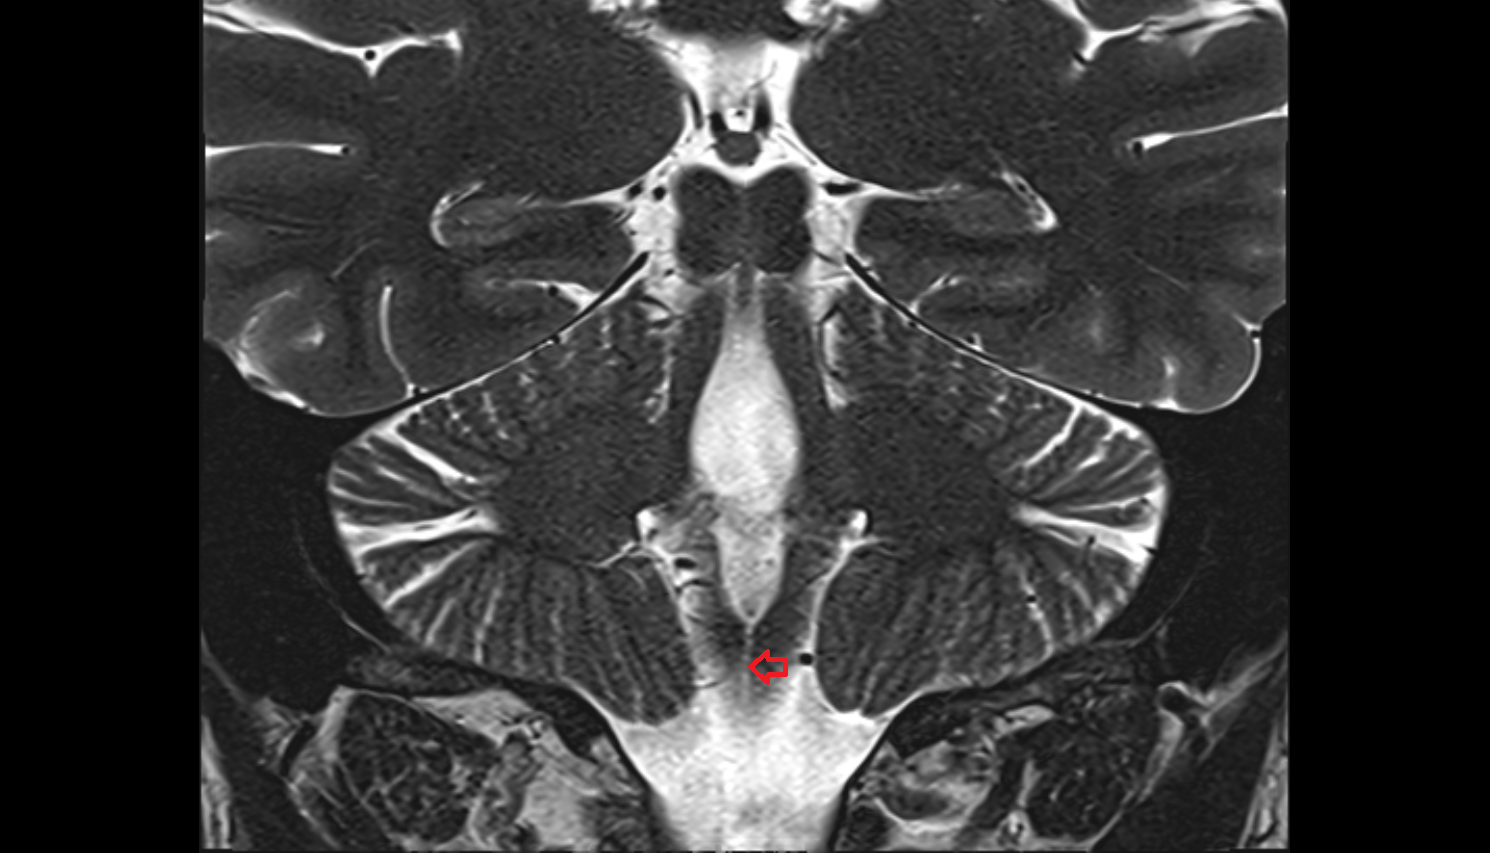

- Median aperture of fourth ventricle (foramen of Magendie)